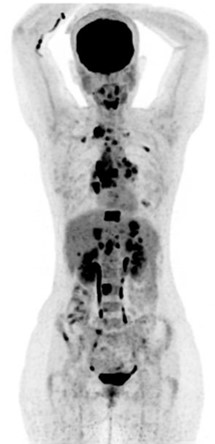

♦ Le TEP Scanner

L’examen : Il faut être à jeun depuis 4 à 6 heures. Une fois arrivé dans le service de médecine Nucléaire, on vérifie la glycémie, branche la perfusion, injecte le radiotraceur puis repos pendant 60 min (fixation tissulaire) et enfin acquisition des images pendant 20 min avec les bras au-dessus des épaules.

IL est utile dans la personnalisation du traitement : permet l’évaluation précoce du traitement dans le cas des Hodgkin ou des grandes cellules B, en fin de traitement selon le type de lymphomes. Il permet également de donner des informations sur une éventuelle transformation en lymphome de haut grade, ou sur une atteinte osseuse. Il ne remplace en aucun cas une biopsie.